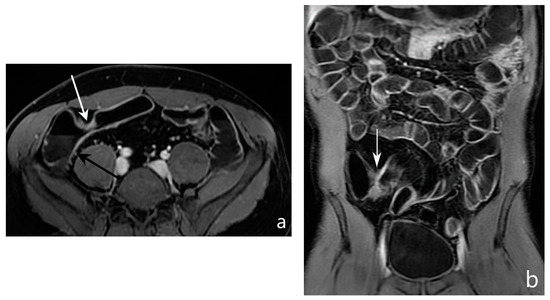

5.3. Fistulising/Perforating Subtype